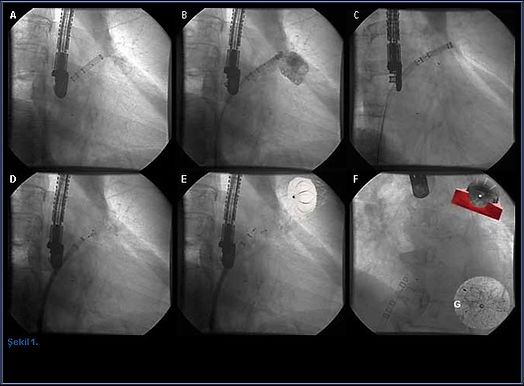

Cihazın implant prosedürü genellikle bir saat sürer ve hasta o günü hastanede geçirir. Hastaya genel anestezi altında transseptal tekniği kullanılarak kateterizasyon uygulaması gerçekleştirilir ve hangi boyutta Watchman cihazının yerleştirileceğini belirlemek için hastanın sol atriyal uzantısı ölçülür. Bunun için ise ekokardiyografi ve bu yöntemin yetersiz kaldığı durumlarda transözofageal ekokardiyogram (TEE) kullanılır. Bu gerekliliğe yol açan durumlar; kalpte pıhtı veya enfeksiyon varlığının araştırılması, yapay kapak işlevlerinin değerlendirilmesi, kalp kapak tamiri veya kalp kapaklarının kapatılması ameliyatları sırasında ve sonrasında ameliyatın başarı durumunu ölçmektir.Doğru boyutlarda cihaz seçildikten sonra Watchman kılıfı, femoral venden girilerek tel üzerinden sol atriyuma ilerletilir. Erişim kılıfı pigtail kateter üzerinden SAA’nın distal kısmına gönderilir. Dağıtım sistemi hazırlanıp erişim kılıfına yerleştirildikten sonra Watchman de SAA’ya yerleştirilir. Cihaz uygulamaya geçmeden önce son kez floroskopi ve TEE ile kontrol edilir. Son olarak cihaz açılır, böylece SAA kapanır ve hastalar operasyon sonunda antikoagülan almayı durdurup inme riskini azaltmış olurlar (1).

Hacettepe Üniversitesi Tıp Fakültesi Kardiyoloji Anabilim Dalı, Watchman cihazının etkinliğini değerlendirmek adına bir çalışma gerçekleştirdi. Oral antikoagülasyon tedavisi için kontrendikasyonu bulunan ve inme gerçekleşme olasılığı yüksek, 8’i erkek 3’ü kadın olan 11 hastaya Watchman cihazıyla perkütan yolla sol atriyal apandis kapatma işlemi uygulandı. Genel anestezi altında gerçekleştirilen işlem floroskopi ve TEE kılavuzluğunda yapıldı. Daha sonra hastalar 6 aylık bir kontrol sürecine girdi.Kontrollerde SAA’da trombüs oluşmadan cihazın kapandığı gözlemlendi. Yalnızca iki hastada cihaz çevresinde 3 milimetreden daha küçük olan kaçak belirlendi fakat bu kaçaklar hastalarda herhangi bir soruna neden olmadı. Sonuç olarak SAA kapatılmasında %100 oranında bir başarı elde edildi. Hacettepe Üniversitesi Tıp Fakültesinin çalışmalarının kısa dönem sonuçlarında, Watchman SAA sisteminin güvenilir ve uygulanabilir bir yöntem olduğu gösterildi.